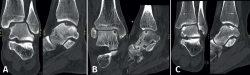

Lesions can be characterized by location, morphology, and size. Location can be described using a 9-grid anatomical scheme of the talus, as described by Raikin et al., shown in Figure 1(14). The morphology of OLTs can be described as crater-like, cystic, or fragmentary (Figure 2)(4,15,16). Lesion size should be reported in anterior-posterior plane, medial-lateral plane, and depth, allowing for calculation of lesion surface area and volume(4). However, there is no consensus on the reporting on morphology of OLTs, and while radiological classification systems for OLTs exist, they lack validation and utilize inconsistent terminology. Moreover, lesion size measurement methods vary, further contributing to inconsistency in lesion characterization in literature(15).

Figure 2. Types of morphologies of OLTs as seen on CT on coronal and sagittal view. A: crater-like; B: cystic; C: fragmentary.